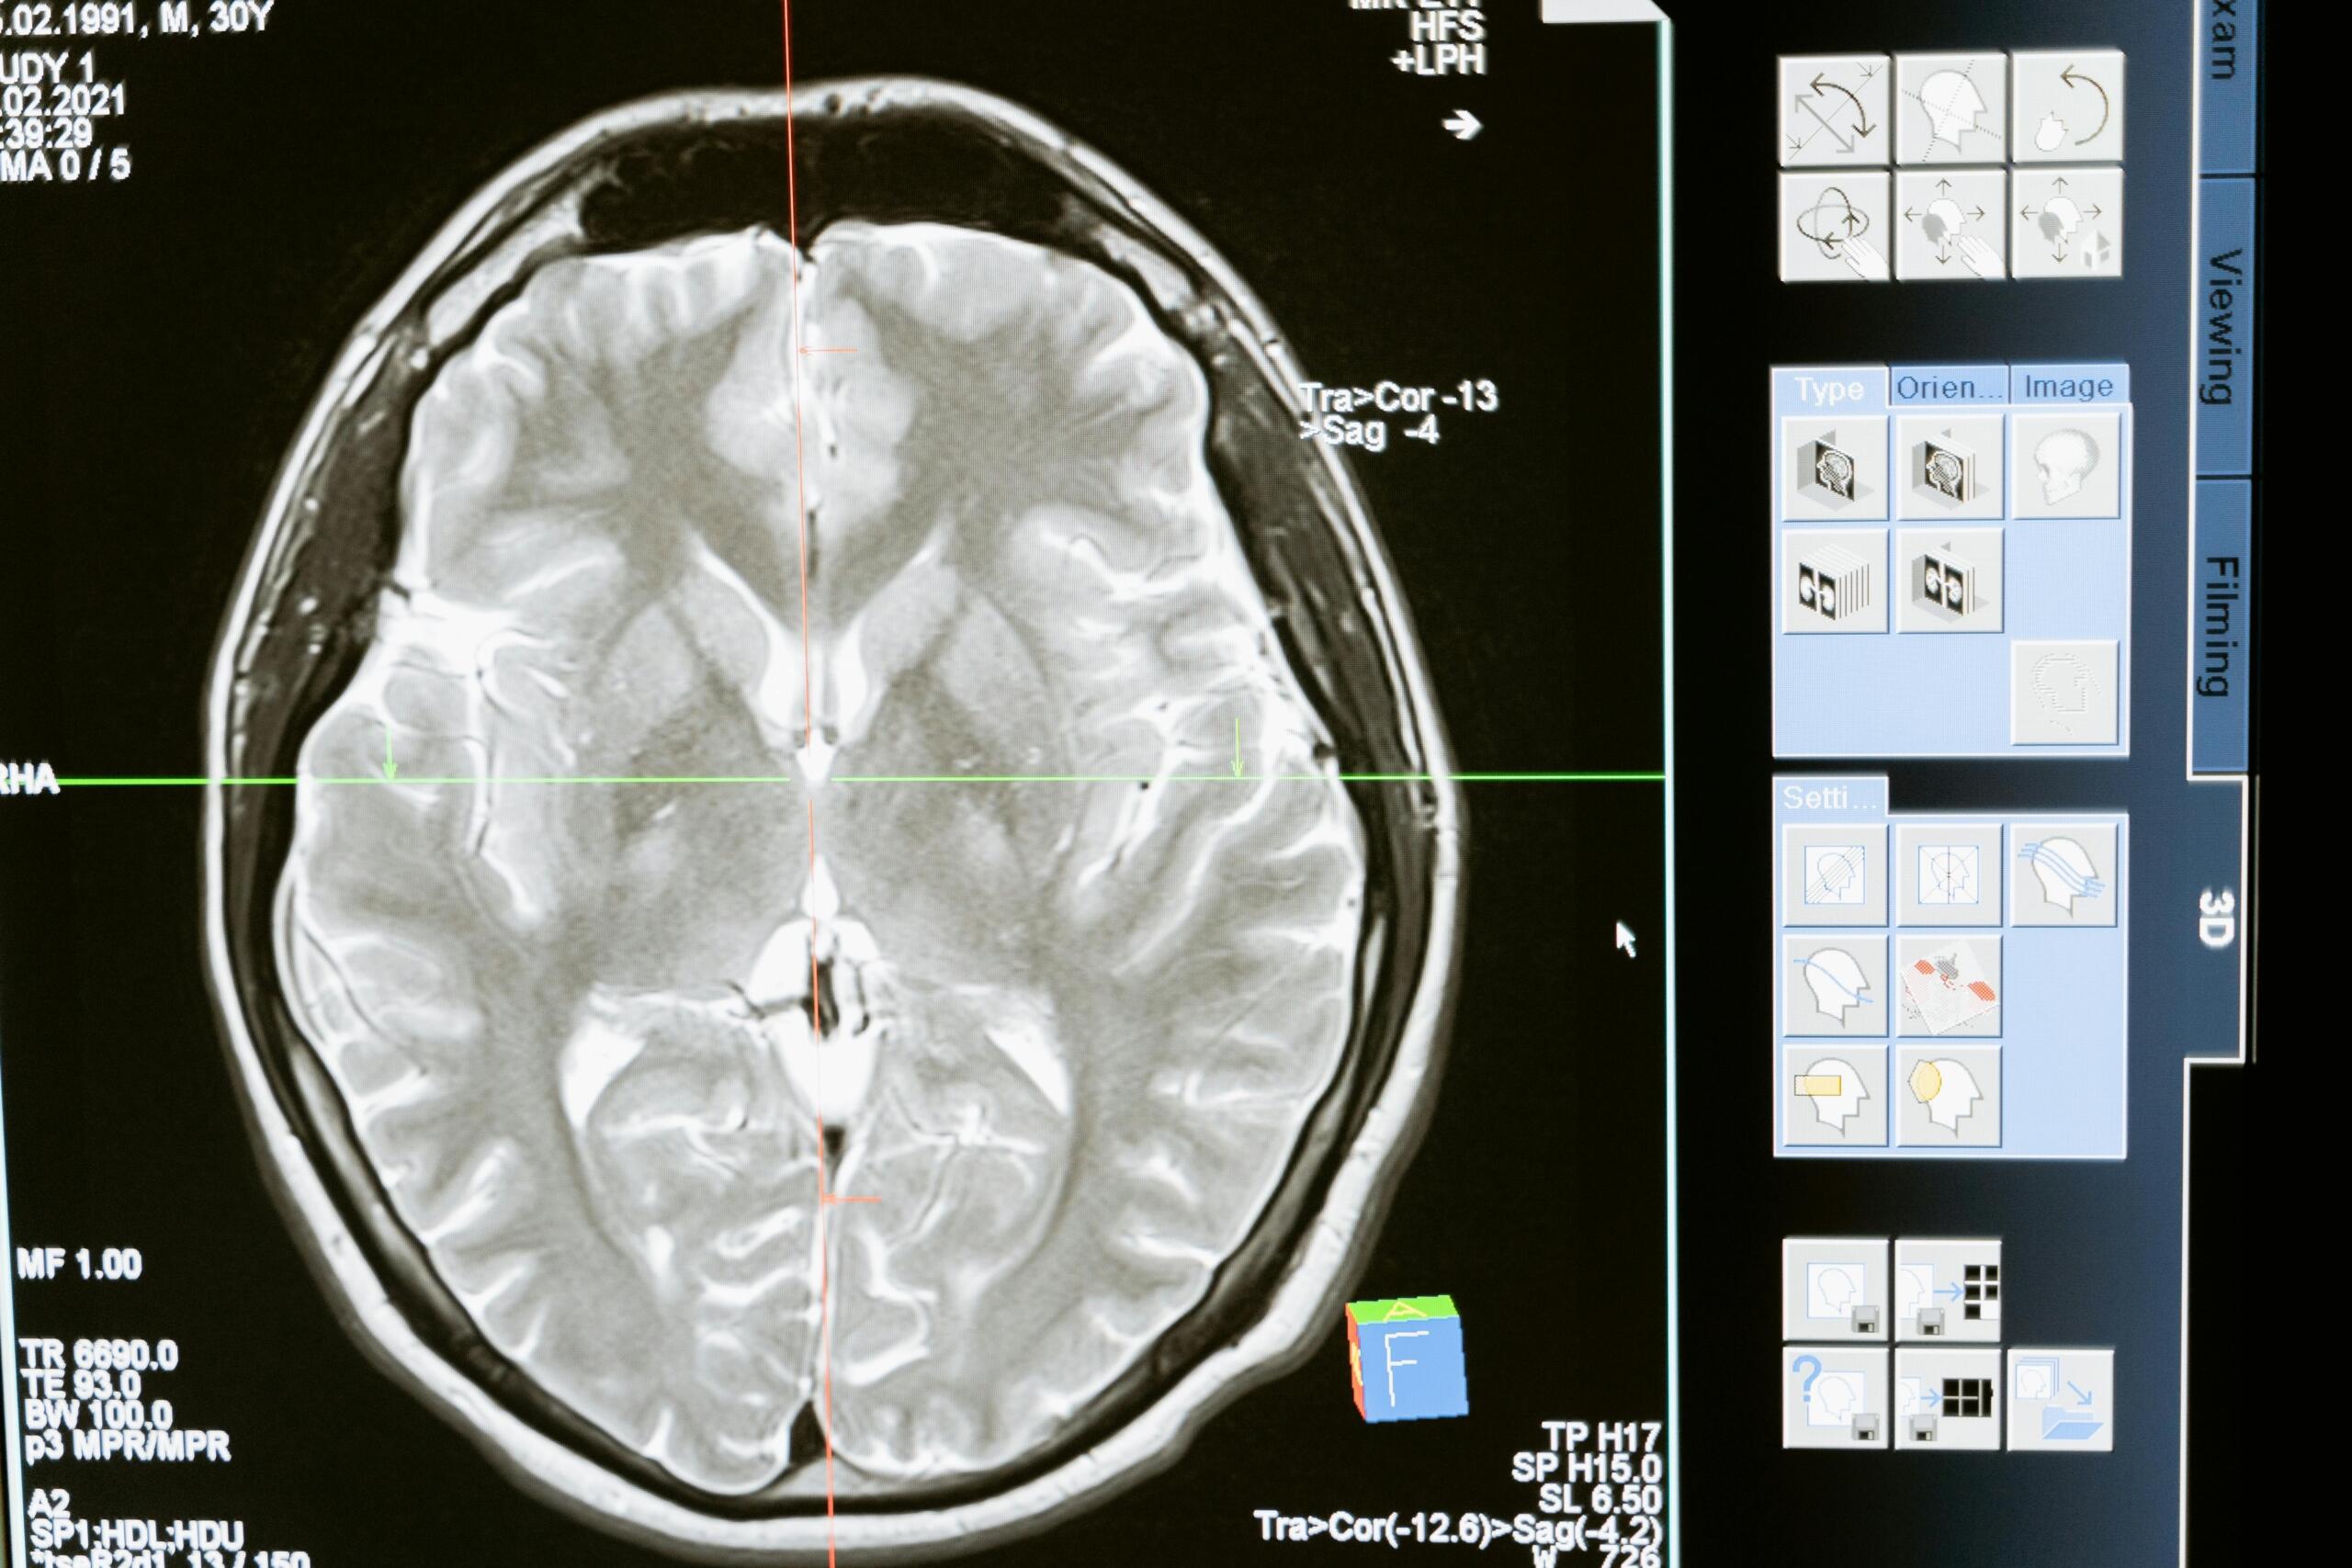

Primjena genske terapije u neurologiji: precizna dijagnostika ključna je za liječenje teških stanja kod kojih standardne metode ne daju rezultate. (Izvor: Pexels.com - Mart Production)